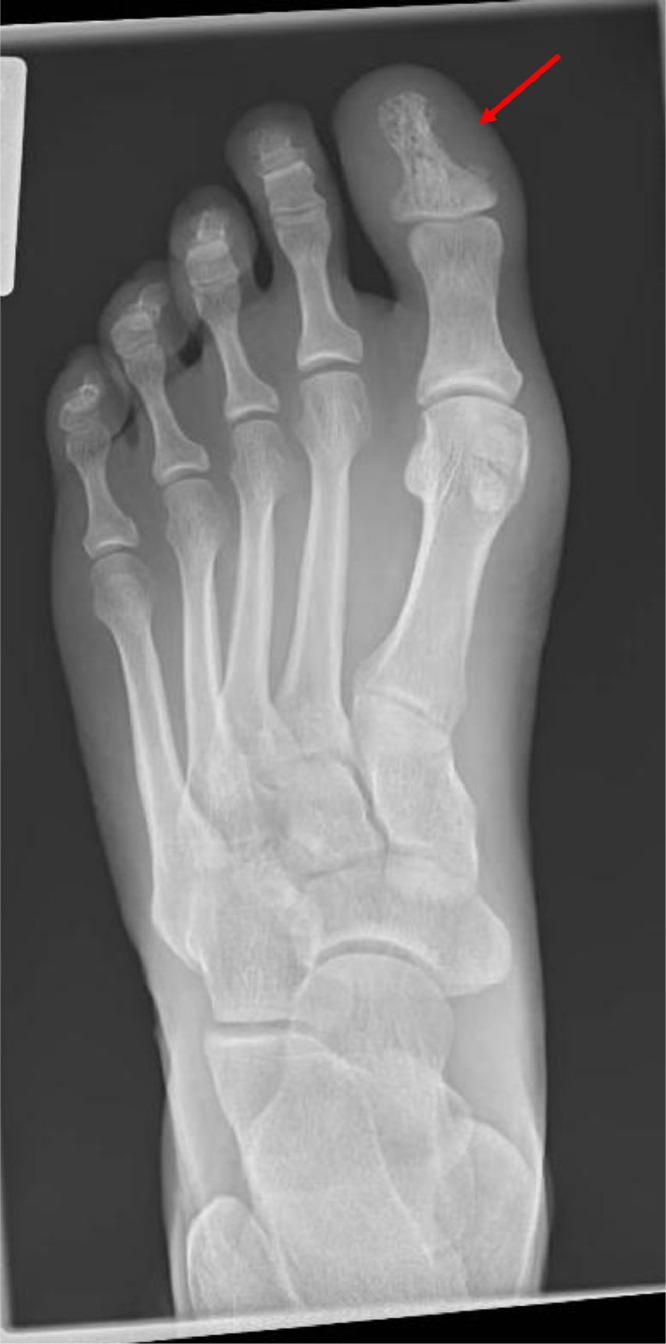

结节病是一种病因不明的复杂疾病,主要累及肺部,但可累及几乎任何器官。由于缺乏特异性标记物,诊断具有挑战性,需要评估临床特征,仔细成像,排除其他条件,理想情况下,组织活检显示非坏死性肉芽肿。超过90%的患者肺部受累,表现为干咳和呼吸困难等症状,以及发烧和体重减轻等全身症状。约30%的病例出现肺外表现,可影响任何器官,包括心脏、神经系统和眼睛。治疗涉及多学科方法,一些患者需要免疫抑制和抗纤维化治疗。尽管通常预后良好,但结节病可导致显著的发病率和死亡率,特别是肺部和心脏并发症。英夫利昔单抗(infliximab)和尼达尼布(nintedanib)等新兴疗法为难治性病例带来了希望,尽管它们存在严重感染和其他副作用的风险。

Sarcoidosis is a complex disease of unknown origin, primarily affecting the lungs but capable of involving almost any organ. Diagnosis is challenging due to the lack of specific markers and requires assessment of clinical features, careful imaging, exclusion of other conditions and, ideally, a tissue biopsy demonstrating non-necrotising granulomas. Over 90% of patients have pulmonary involvement, presenting with symptoms like dry cough and breathlessness, along with systemic signs such as fever and weight loss. Extrapulmonary manifestations occur in about 30% of cases and can affect any organ, including the heart, nervous system and eyes. Management involves a multidisciplinary approach with some patients requiring immunosuppressive and antifibrotic therapies. Despite generally good outcomes, sarcoidosis can lead to significant morbidity and mortality, particularly from pulmonary and cardiac complications. Emerging treatments like infliximab and nintedanib offer hope for refractory cases, although they carry risks of serious infections and other side effects.